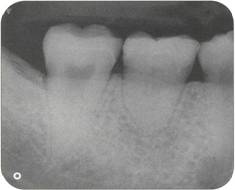

Fi 545e45f g 5-8i Radiographic evaluation of the donor tooth. Several angulations should be used to determine the likely fit of the donor tooth into the recipient site. If the first premolar is double-rooted, consider using the second premolar as a donor tooth. |